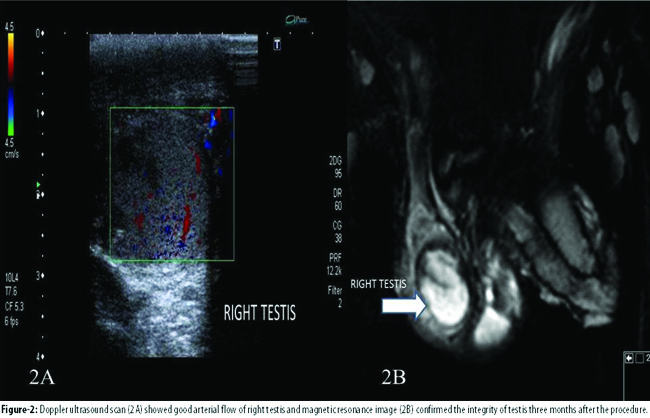

Follow-up DUSS at first month showed a viable testis with no atrophic changes. At postoperative third month, DUSS demonstrated a good arterial blood flow (Figure-2A)

and magnetic resonance imaging (MRI) revealed normal integrity and volume of the right testis (Figure-2B). Physical examination was also normal. No complications were detected during the follow-up period.